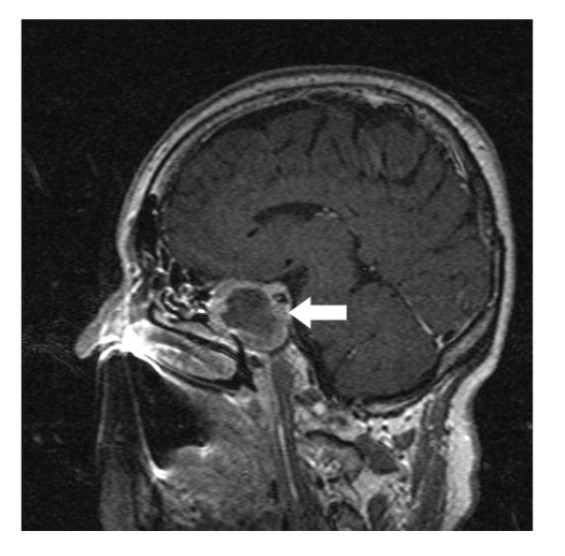

A 64-year-old lady presented to the outpatient department with complaints of headache and right eye blurring of vision for one month. Neurological examination revealed that bitemporal hemianopsia and impairment of visual acuity. Findings from fundus examination were within normal limits. Rest of the brain appeared unremarkable. Endocrine evaluation was normal. Results of renal function tests, liver function tests and haemogram test were within normal limits. A clinical diagnosis of non-secretory pituitary adenoma was made. Magnetic resonance imaging showed a well-circumscribed contrast-enhancing lesion in the sella (Figure 1, Figure 2). The patient underwent an endoscopic endonasal/transsfenoidal surgery in the supine position and total lesion resection was peformed. Intraoperatively, the lesion was found to be yellow colour, soft and avascular and it was removed totally until the sella turcica was visualized (Figure 3).In histopathologic examination septate hyphae were observed between inflammatory cells, Grocott staining is positive, but acid-fast stain for acid-fast bacilli (AFB) was negative. Histopathological findings suggest that infection of Actinomyces (Figure 4, Figure 5). We performed to patient consulted by patients to infectious diseases clinic. Patients underwent intravenous 6x2 gr ampicillin for four weeks.Then oral 4X500 mg amoxicillin treatment is planned a for at least 6 months. Patient did not have any deficits in the next six months.

Figure 1.White arrow shows on sagittal section of MRI that a well-circumscribed contrast-enhancing lesion in the sella